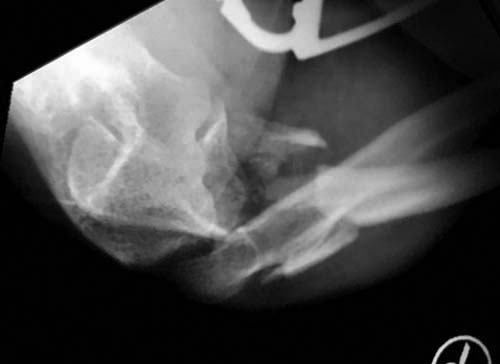

Добрый день, коллеги. Какие мнения будут по этому снимку?

А так, здесь имеется многофрагментарный проксимальный перелом локтевого отростка с переломо-вывихом головки лучевой кости по классификации Mason III. Решение принимается на основании КТ срезов, потому что на боковом рентген снимке вроде отсутствует смещение, где сустав и контур Coronoid в одном блоке, а на прямом подозрение на смещение в Coronoid?